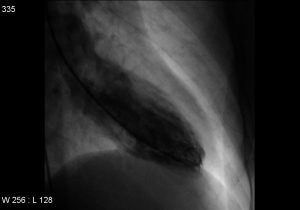

”Det første, vi som læger gør, er at undersøge hjertets kranspulsårer for at se, om der sidder en blodprop i hjertets blodkar – det vil der ikke gøre hos en patient med Broken Heart Syndrome. Dernæst foretager vi en ultralydsscanning for at få en fornemmelse af, hvordan hjertet pumper, og her vil man se, at hjertemusklen trækker sig sammen på en speciel måde. Forestil dig, at spidsen og den midterste del af hjertets for- og bagvæg ikke trækker sig sammen. Hjertet er med andre ord helt slapt nedadtil og pumper normalt opadtil.”

Sagt med andre ord pumper hjertet ikke, som det skal, og det er ikke bare noget, der kan mærkes, det er sådan set også noget, der kan ses. Thomas Emil Christensen beskriver, at hjertet får form som en vase, simpelthen fordi dele af hjertet holder op med at slå, og at dets venstre hovedkammer svulmer op.